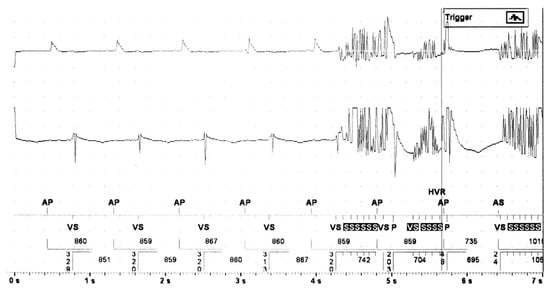

3.7. Oversensing and Potential EMI

Artifacts related to myopotential oversensing were detected in a patient without in-house pre-interventional device interrogation with a magnet inactivated CRT-D, undergoing uneventful implantation of an endovascular popliteal stent-prothesis without cauterization. During the post-operative follow-up, the ventricular sensitivity was reprogrammed, and the LV lead had to be inactivated due to a low phrenic nerve capture threshold.

There was only one CRT-D patient with documented non-physiologic short VV intervals potentially caused by EMI detected during neck surgery for local abscess using monopolar electrocautery. In this case, antitachycardia therapy had been deactivated before surgery, and no ADE occurred.